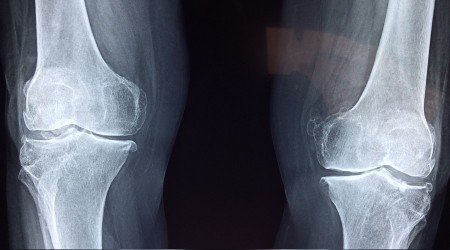

Ortopedi ve Travmatoloji Uzmanı Op. Dr. Cuma Kayıkçı, “Diz eklemindeki kireçlenmenin erken evrelerinde PRP enjeksiyonları ile hastaların ağrılarında azalma ve fonksiyonlarında düzelme yaşanmıştır. Bununla birlikte topuk dikeninde, tendinitlerde de PRP ile başarılı sonuçlar elde edilmiştir” dedi

PRP uygulamalarını ortopedi ve travmatoloji bölümünde hastalarda başarılı bir şekilde uyguladıklarını sonuçlarının çok iyi olduğunu ifade eden Ortopedi ve Travmatoloji Uzm. Op. Dr. Cuma Kayıkçı, "PRP (PlateletRichPlasma) ya da diğer adıyla Trombositten Zengin Plazma, kişinin kendi kanından hazırlanan ve tıbbın birçok alanında iyileşmeyi uyarmak ve düzenlemek için kullanılan bir yöntemdir. Kullanımda olan onlarca PRP hazırlama kiti yardımıyla, hastadan 10-60 ml arasında kan alınır ve santrifüj edilir.

PRP, özellikle trombositten zengin bir sıvı elde edilmesidir. Daha sonra vücudun neresinde sıkıntı varsa diyelim ki dizde, omuzda, kalçada kireçlenme varsa oraya o sıvının enjekte edilmesi işlemidir. Trombositten zengin olduğu için özellikle lezyonu olan bölgedeki iyileştirici hücreleri tekrardan aktive ediyor. Hücreleri aktifleştirdiği için hücreler tekrardan yenileniyor. Bu durum da hastalıklı bölgelerin iyileşmesini sağlıyor" sözleriyle PRP uygulamasının hücre yenileme özeliği olduğuna dikkat çekti.

Op. Dr. Cuma Kayıkçı, PRP uygulamalarını ortopedi ve travmatoloji bölümünde hastalarda başarılı bir şekilde uyguladıklarını, sonuçlarının çok iyi olduğunu belirtti. Dr. Kayıkçı, uygulama alanları hakkında şu açıklamalarda bulundu: "Erken dönem diz kireçlenmelerinde, tenisçi dirseğinde PRP uygulamaları ile başarılı sonuçlar elde edilmiştir. Benzer şekilde aşil tendon hastalıklarında, kronik patellar tendon yaralanmalarında ve plantar fascitis hastalığında. Sporcularda sık görülen bağ yaralanmaları sonrası PRP enjeksiyonları ile daha hızlı iyileşme söz konusu. Kas yaralanmalarında, diz eklemindeki kireçlenmenin erken evrelerinde PRP enjeksiyonları ile hastaların ağrılarında azalma ve fonksiyonlarında düzelme yaşanmıştır. Bununla birlikte topuk dikeninde de PRP ile başarılı sonuçlar elde edilmiştir."